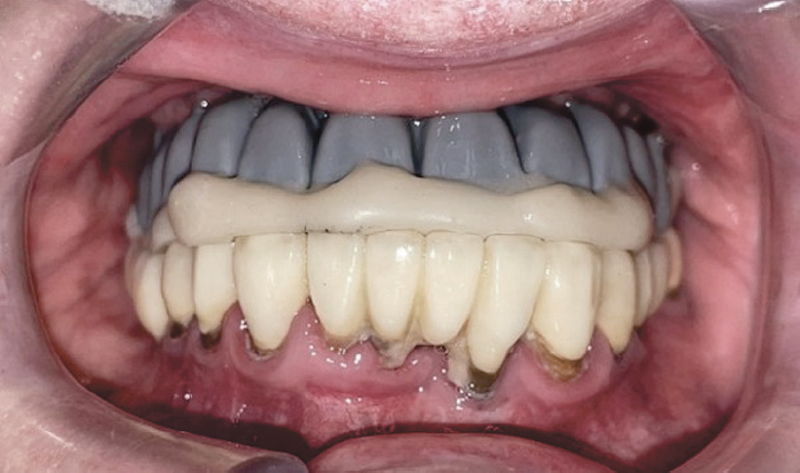

В программе «Exocad» (Exocad, Германия) проведено моделирование временных реставраций (рис. 15, 16). Затем методом фрезерования изготовлены временные коронки из пластмассы ППМА. Вклеены стандартные абатменты, которые использовались в прототипе (рис. 17).

Рис. 15. Компьютерное моделирование временных реставраций, вид спереди

Fig. 15. Computer modelling of temporary restorations, front view

Рис. 16. Компьютерное моделирование временных реставраций, вид окклюзионной поверхности и вид слева

Fig. 16. Computer modelling of temporary restorations, view of the occlusal surface and left view

Рис. 17. Временные пластмассовые коронки

Fig. 17. Temporary plastic crowns

На рисунках 18, 19 изображены временные коронки в полости рта.

Рис. 18. Фотографии временных коронок на имплантатах в полости рта

Fig. 18. Photographs of implant-supported temporary crowns in the oral cavity